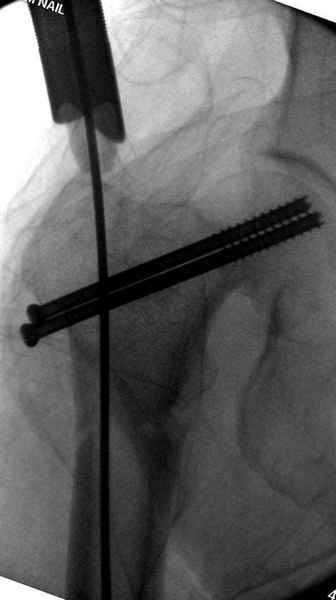

На второй день после выписки упал дома. Снимки приложены. Коллеги рекомендуют удаление шурупа и вытяжение. Что делать?

Правильно, ситуация изменилась, как говорят у нас теперь "different animal", надо решать проблему подвертельного перелома. При наличии различных вариантов фиксаторов, включая Страйкер Гамма 3, мы выбрали DePuy Antegrade Trachanteric Nail из-за многовариантности проксимальной фиксации и двойного изгиба. Вводится через вертел под 8 градусным углом, и есть достаточный передний диафизарный изгиб, предупреждающий пенетрацию дистального переднего кортекса.

Но ведь и головка бедра сползла в варус - отчего ограничились только фиксацией подвертельного перелома, а не убрали винты и не сделали репозицию шейки?